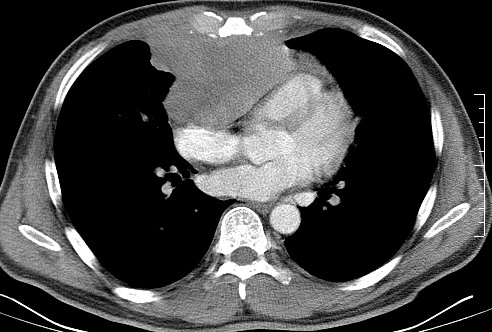

男   40   反复腹痛入院行彩超检查示胸骨右缘4、5肋间不均质回声团

淋巴瘤:前纵隔可见多组肿大的淋巴结,部分融合,有液化坏死

上区却那么有点象占位,胸腺瘤不太象,一点强化也没有,淋巴瘤气管前上腔静后却很干净,下区也点象纵隔积血征,

莲蓬籽征  考虑淋巴瘤